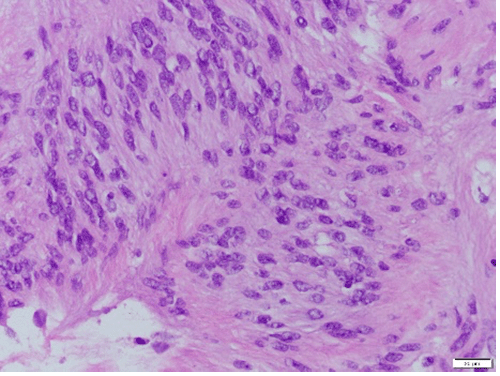

Haemotoxylin and eosin (H&E) staining at 40x magnification demonstrates characteristic hypercellular palisading pattern around fibrillary process commonly found in schwannomas

A macroscopic examination of the specimen revealed non-necrotic tissue with multiple cystic spaces containing hemorrhagic material. Pathology of the specimen identified the mass as a gastric schwannoma with a characteristic hypercellular palisading pattern around a fibrillary process on hemotoxylin and eosin (H&E) staining. IHC demonstrated diffuse positive expression of S100 and SOX10, confirming the diagnosis of gastric schwannoma (Figure 3).